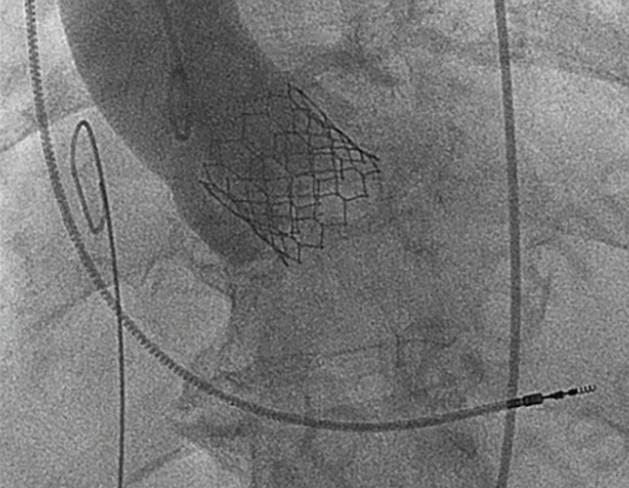

The treatment of native aortic valve regurgitation with a TAVR procedure is also under discussion at TVT. Dr. Agarwal described acute and chronic aortic regurgitation in detail. Acute aortic regurgitation may result from an abnormality of the aorta or aortic valve leaflets (possibly due to endocarditis), an iatrogenic injury (arising after transcatheter procedures), or blunt chest trauma. Chronic aortic regurgitation can arise from the presence of bicuspid aortic valves, aortic disease, rheumatic disease, or calcific aortic disease. Dr. Agarwal described how “TAVR for isolated, chronic aortic regurgitation is challenging, because of dilation of the aortic annulus and aortic root,” noting also that “there is a lack of adequate leaflet calcification for anchoring.” Risks from TAVR to treat aortic regurgitation include valve migration and paravalvular leak. Two recent large database studies (Medicare and National [Nationwide] Inpatient Sample [NIS]) compared TAVR and surgical aortic valve replacement for native aortic valve regurgitation. The studies showed similar 30-day mortality between the two procedures, and the NIS database study showed TAVR with more favorable hospital outcomes including for acute kidney injury and cardiogenic shock. The Medicare database study demonstrated an increased risk of mortality, redo aortic valve replacement, stroke, and endocarditis for TAVR patients at 31 months. Dr. Agarwal concluded with the case of a 65-year-old male with severe aortic regurgitation who received a JenaValve (currently investigational use only), with the use of 3D echo and CT assessment and guidance.